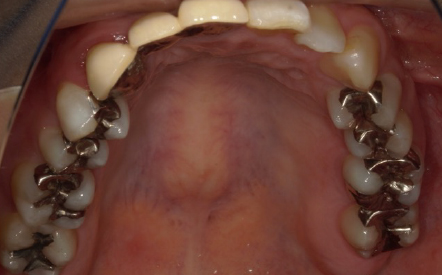

「入れた被せものの色が気になる 過去銀歯による治療を受けてきたが、再発を繰り返している。

見た目も気になるのでしっかり治したい」

→全顎的に補綴物の不適多数。多数歯に2次カリエス(虫歯)。咬合も不正。

Before